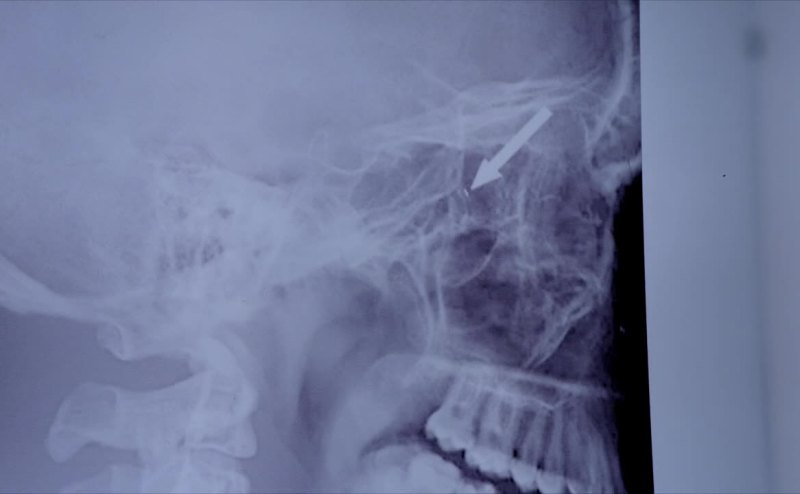

The eye is the most confined space in the body,

which means the camera's probably 3 to 4 millimeters long

and difficult to see without a microscopic lens.

That must be the unidentified splinter the MRI showed.

It's an ocular nano-implant.